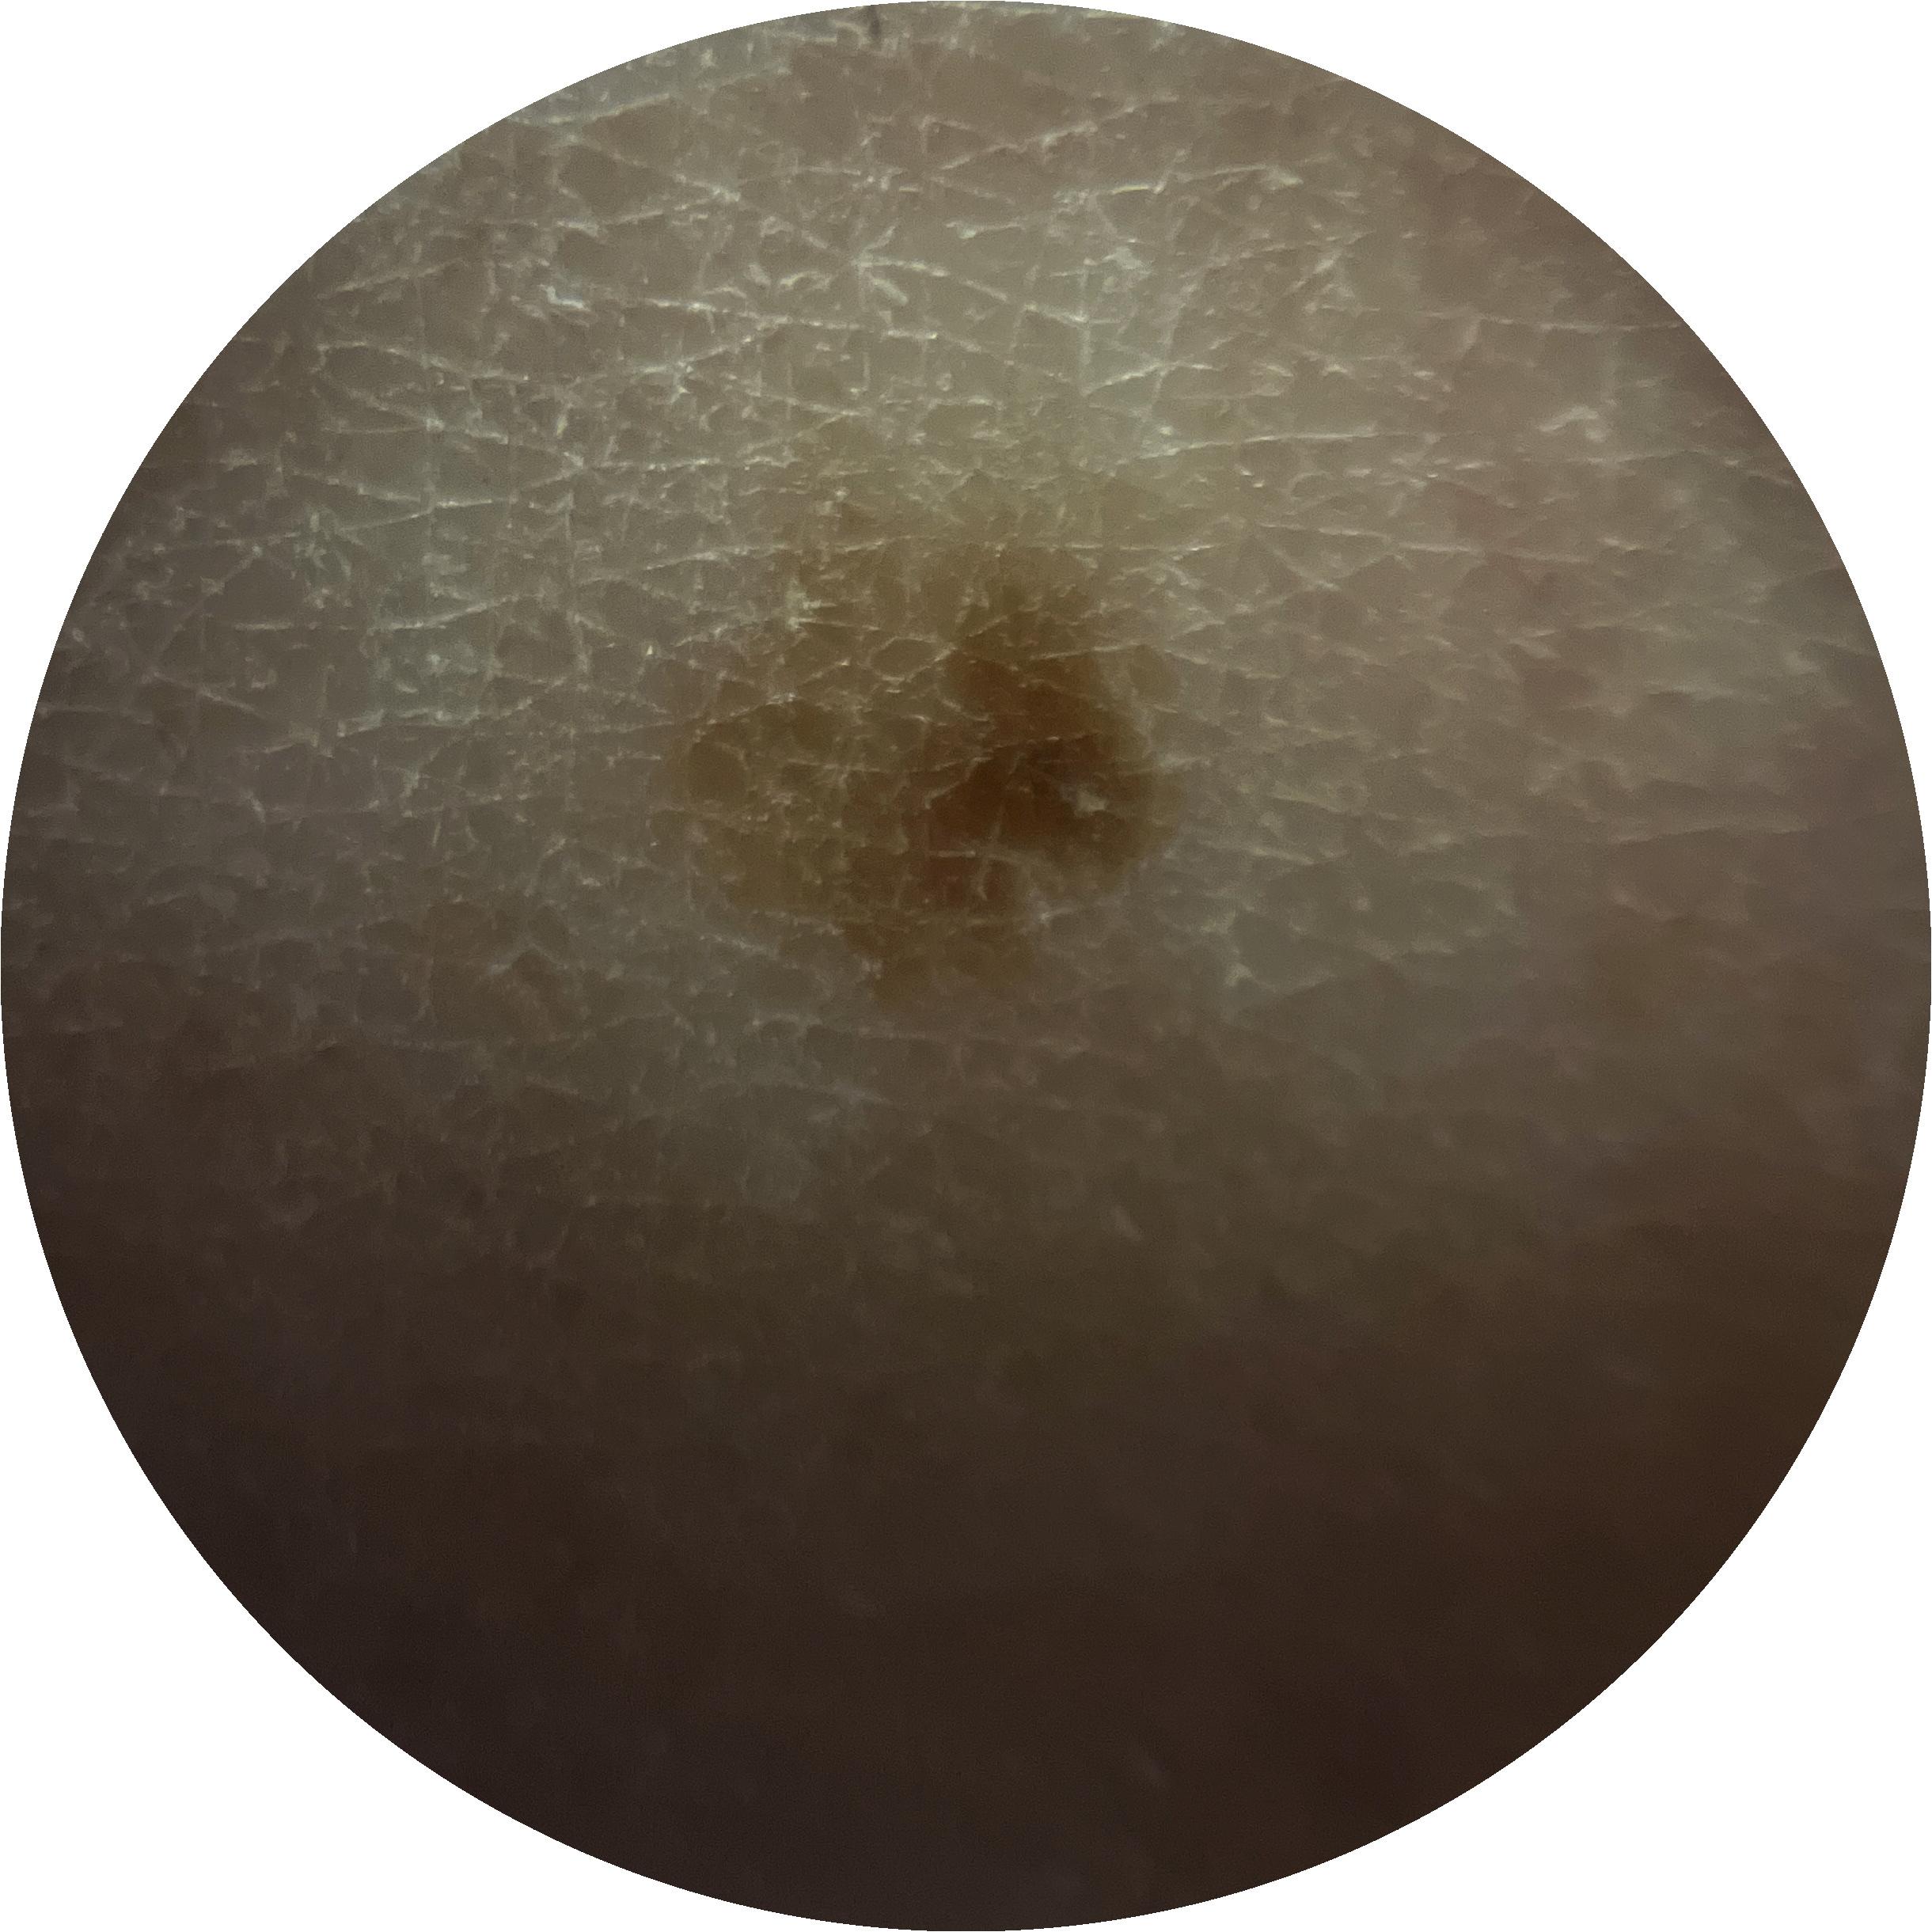

ISIC_7213120

acquisition_day 277

age_approx 70

anatom_site_1 Lower extremity

anatom_site_general lower extremity

diagnosis_1 Benign

family_hx_mm True

fitzpatrick_skin_type I

image_manipulation instrument only

image_type dermoscopic

lesion_id IL_3605610

patient_id IP_0257923

personal_hx_mm True

sex female